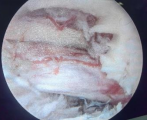

6.显微镜下脊柱椎管内肿瘤切除技术

椎管内肿瘤是指发生在脊髓、脊神经根、脊膜和椎管壁组织的原发性或继发性肿瘤,主要表现为阵发性疼痛及肢体感觉异常。根据肿瘤与脊髓、硬脊膜的位置关系可分为髓内肿瘤、髓外硬脊膜下肿瘤和硬脊膜外肿瘤。椎管内肿瘤是脊柱外科的常见病,可发生于任何年龄,多见于中年人。我院常规开展显微镜下颈椎、胸椎、腰椎椎管内肿瘤摘除术,在显微镜的帮助下逐层绕开皮下组织、肌肉、到达椎骨以后只需要开个小口就能进入椎管,找到肿瘤,然后将它一点点地清除。